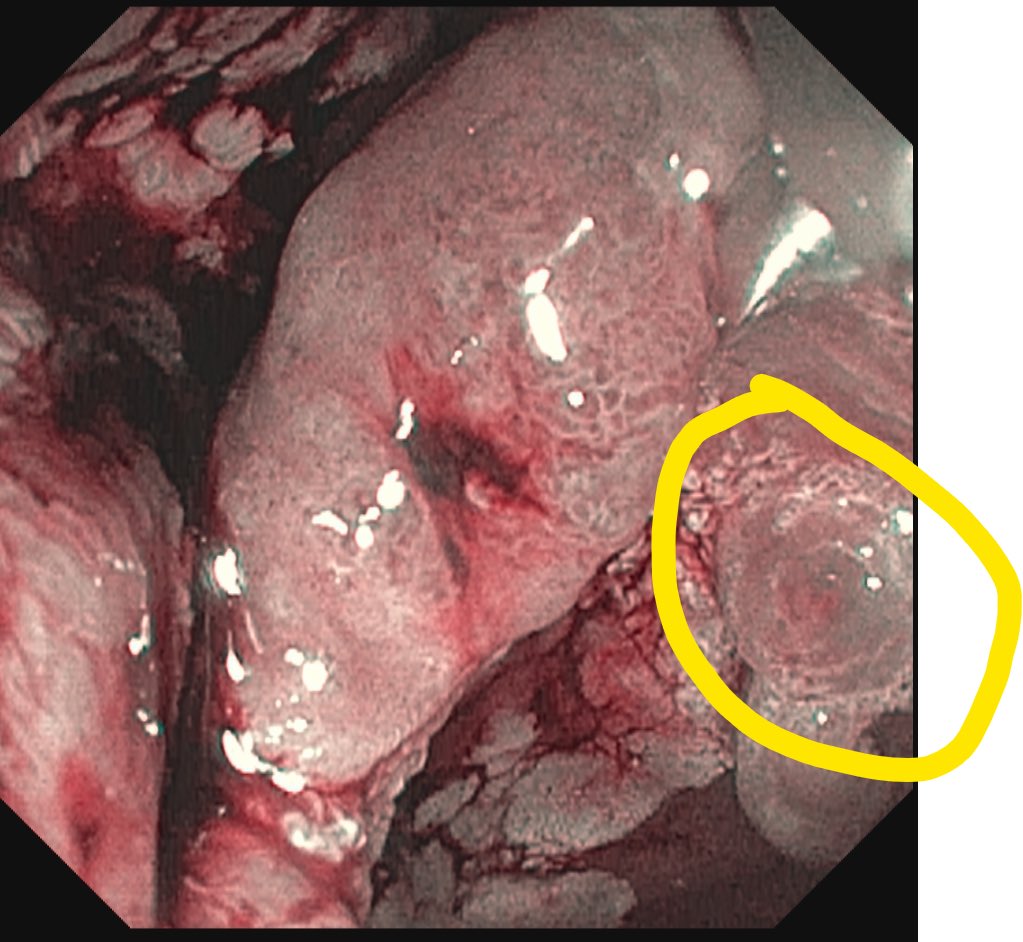

43-year-old fitness influencer ignored her GI symptoms for a year. Then she was diagnosed with stage 4 colon cancer: ‘It could happen to anyone’ fortune.com/well/article/c…